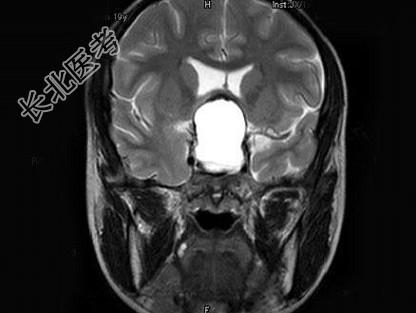

- 单项选择题男,19岁, 视力模糊1周,MRI检查如图所示应诊断为 ( )

A、颅咽管瘤

B、脑膜瘤

C、垂体瘤卒中

D、脑膜膨出

E、未见异常